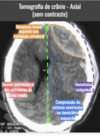

Qual a sequência de tecidos até chegar no parênquima cerebral?

Abaixo do crânio, o que temos?

Espaço epidural/Extradural

Abaixo da dura-mater, o que temos?

Abaixo do espaço subdural, o que temos?

Abaixo da aracnóide mater, o que temos?

Abaixo do espaço subaracnoídeo, o que temos?

Abaixo da pia mater, o que temos?